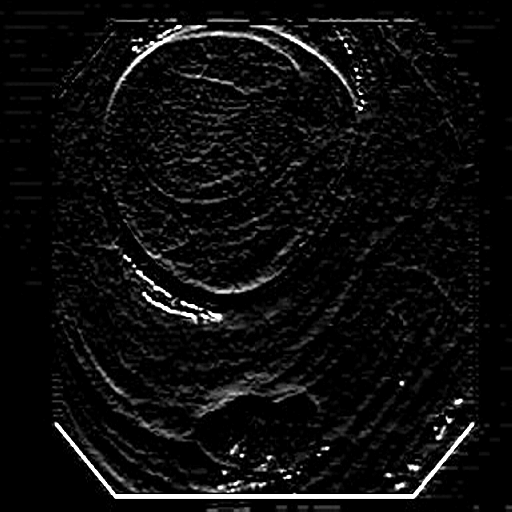

(a) Polyp 1

Refer to caption

(b) Sobel x

(c) Sobel y

(d) Sobel xy

(e) Polyp 2

(f) Sobel x

(g) Sobel y

(h) Sobel xy

Fig. 3: Edge maps of the Sobel operator in x-y directions

The Edge-Guided Feature Enrichment (EGFE) unit actively enhances feature representation by integrating edge knowledge into the set of features. It applies a Sobel operator to the input feature set, generating separate gradient magnitude maps for horizontal (𝒮x)subscript𝒮𝑥(\mathcal{S}_{x})( caligraphic_S start_POSTSUBSCRIPT italic_x end_POSTSUBSCRIPT ) and vertical (𝒮y)subscript𝒮𝑦(\mathcal{S}_{y})( caligraphic_S start_POSTSUBSCRIPT italic_y end_POSTSUBSCRIPT ) directions (Fig. 3). As illustrated in Fig. 3, the Sobel operation in a single direction captures limited information about the polyp. However, combining these maps (Fig. 3(d) and Fig. 3(h)) effectively captures polyp boundaries and enriches learned features. The final gradient magnitude map, produced using the Euclidean norm (Eq. 1), highlights regions with significant intensity changes at polyp boundaries.